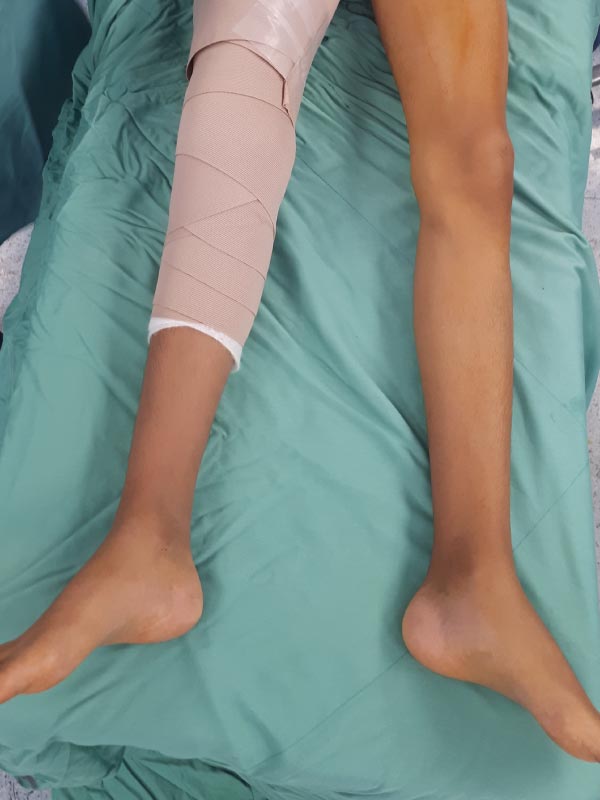

Caso No. 2 - Enfermedad de Blount derecha

Preoperación

Posoperación

Enfermedad de Blount derecha

Diagnóstico: Enfermedad de Blount derecha (deformidad mixta de la tibia tanto frontal y rotacional)

Tratamiento quirúrgico: osteotomía correctiva y fijación externa Taylor Spatial Frame